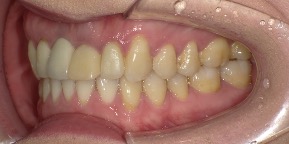

30歳女性のビフォーアフター

| 診断 | 叢生 |

| 治療方針 | 治療方針:インビザラインシステムにて主にIPR(歯と歯の間をわずかに削合してスペースを獲得する方法)を組み込んだ動的矯正治療を行い、叢生を改善後、保定を行う。 |

| 治療費 ※ | 96万5千円(診断、型取り、矯正中のメンテナンス、保定装置を含む料金) |

| 治療期間 | 1年8か月 |

| リスク | 1日20時間以上マウスピースを使用できない場合、歯が動かなかったり、想定しない誤差により不完全に終わる可能性がある。装着時や食事時に痛みを伴う。歯肉退縮や虫歯になるおそれがある。また、指導通りに装着できていない場合や適切なブラッシングが出来ていないとそのリスクが高くなる。歯根が短くなることがある。ごくまれに歯の神経が損傷してしまうことがある。過去にぶつけたり深い虫歯治療をしたことがあるとそのリスクはやや高くなる。矯正後には保定装置が必要。適切な使用ができない場合、後戻りの原因となる。将来的に歯並びが動いて再矯正が必要な場合がある。舌癖(舌で歯を押し出す癖)親知らずが正常に生えていない場合、その可能性がやや高くなる。 |